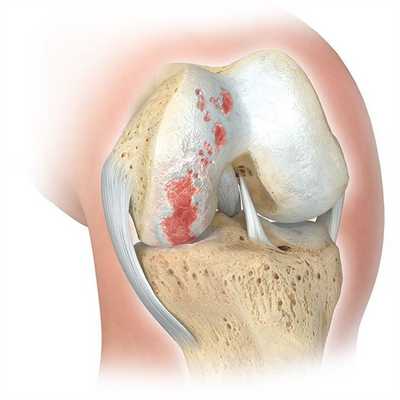

Деформирующий остеоартроз — одно из ведущих заболеваний опорно-двигательного аппарата. Он проявляется дегенеративно-дистрофическими изменениями суставных поверхностей. Частота встречаемости составляет от 3 до 12% среди взрослого населения. В этом показателе на первом месте стоит поражение тазобедренного сустава, а на втором - коленного.

Если сустав поражен указанным на изображении образом, то возможна его частичная замена.

Основной метод лечения - постановка эндопротеза вместо поврежденного сустава. Раньше выполнялось преимущественно тотальное эндопротезирование коленного сустава, однако сейчас активно развивается другое направление - одномыщелковое (частичное) эндопротезирование.

Динамика разрушения хрящевой поверхности.